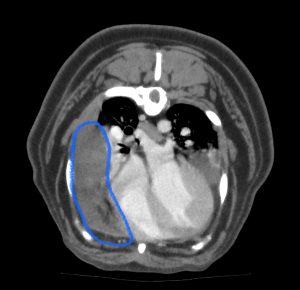

持参されたCTを拝見したところ、右前葉の腫大、内部に細かい泡、血行不良、胸水貯留が認められ、右前葉の肺葉捻転と診断しました。

青丸=大量の胸水